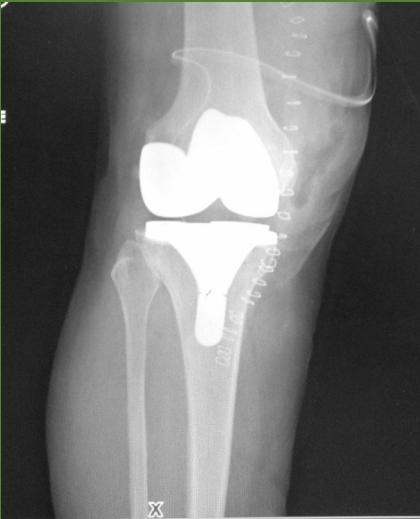

Surgical Considerations

- Timing: When conservative measures fail

- Options:

- Arthroscopy (selective cases)

- Osteotomy (young patients with unicompartmental disease)

- Total knee arthroplasty (end-stage disease)